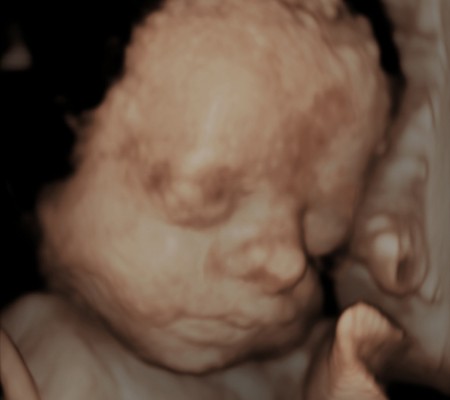

3D i 4D tehnologija omogućava da vidimo površinu bebe na lepši način i pokrete ploda u realnom vremenu.

Takođe nam omogućava da bolje vidimo fetalne mane na licu, šakama i stopalima.

Kao i 2D, 3D i 4D koriste ultrazvučni talas da se kreira slika bebe u materici. 3D je kreirana slika u prostoru dok 4D prikazuje pokret unutar materice pa možemo videti kako se beba smeje, mršti ili zeva.

Da bi se dobile dobre slike poželjno je da se pregled radi između 24 i 32 nedelje trudnoće.